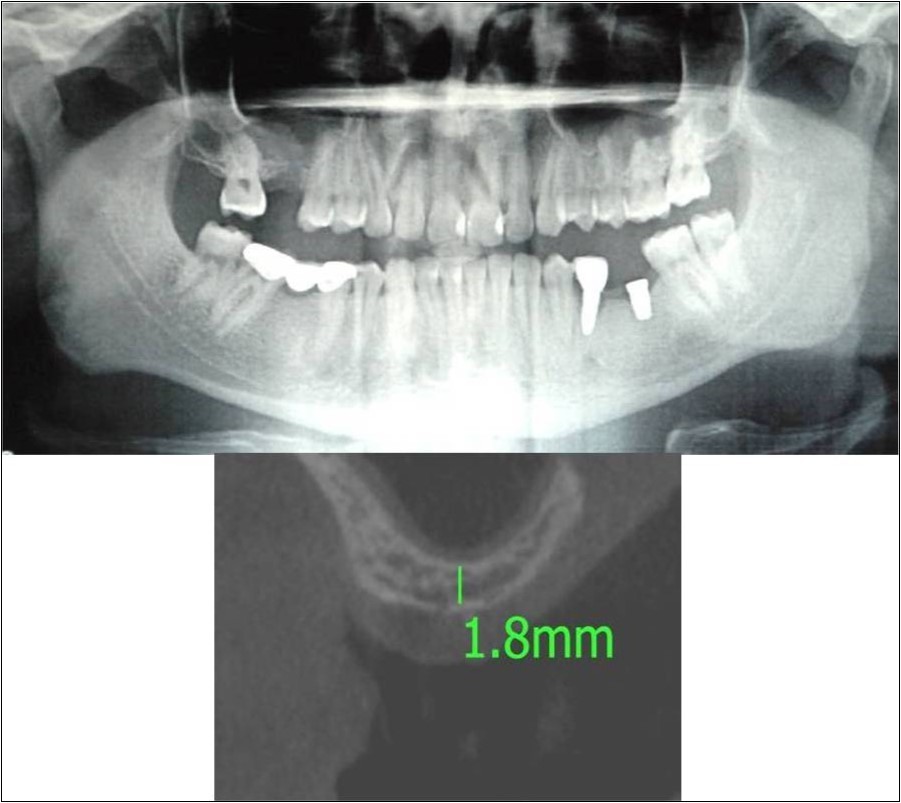

Case Report 6:

A 25 years old young male patient reported to the Department of Oral and Maxillofacial Surgery, D.A.P.M.R.V Dental College and Hospital seeking options for implant supported prosthesis for rehabilitation of missing right first molar. The tooth was extracted 6 months ago because of gross loss of tooth structure and poor prognosis for root canal treatment. Patient did not give history of any existing sinus pathologies. All possible rehabilitative options were explained to the patient and a treatment plan of replacement of missing tooth with implant supported prosthesis was finalized.

Clinical and Radiological Assessment:

1.Partially edentulous maxillary arch with missing 16;

2.Increased pneumatisation of right and left maxillary sinus;

3.Height of available bone- 1.8mm;

4.Transverse thickness of available bone (CBCT evaluation)- 6.2mm;

5.Implant supported prosthesis i.r.t 35 and 36;

6.Fixed partial denture i.r.t 45, 46, 47;

7.Inter-ridge space adequate to place implant (12mm).

Treatment:

Patient underwent the procedure of direct sinus elevation using sinus lateral approach kit. After crestal and vertical release incisions, muco-periosteal flap was raised to expose the buttress region. A bony window of 1cm diameter was created; sinus lining identified and elevated up to receive calcium phosphosilicate as graft material and closure was achieved under local anaesthesia and strict aseptic protocols. Implant placement was planned to be carried-out after a period of 6 months to allow for the consolidation for graft and naive bone formation. At the end of 6 months, a repeat CBCT scan was advised to evaluate the increase in bone height. (Figure 17a,b, pre-treatment; Figure 18a,b, post-treatment)

Figure 17.a,b. Pre-treatment OPG and cross section of CBCT showing residual alveolar bone height for Case No.6;

Figure 18.(a,b) Post-treatment OPG and cross section of CBCT showing residual alveolar bone height for Case No.6;